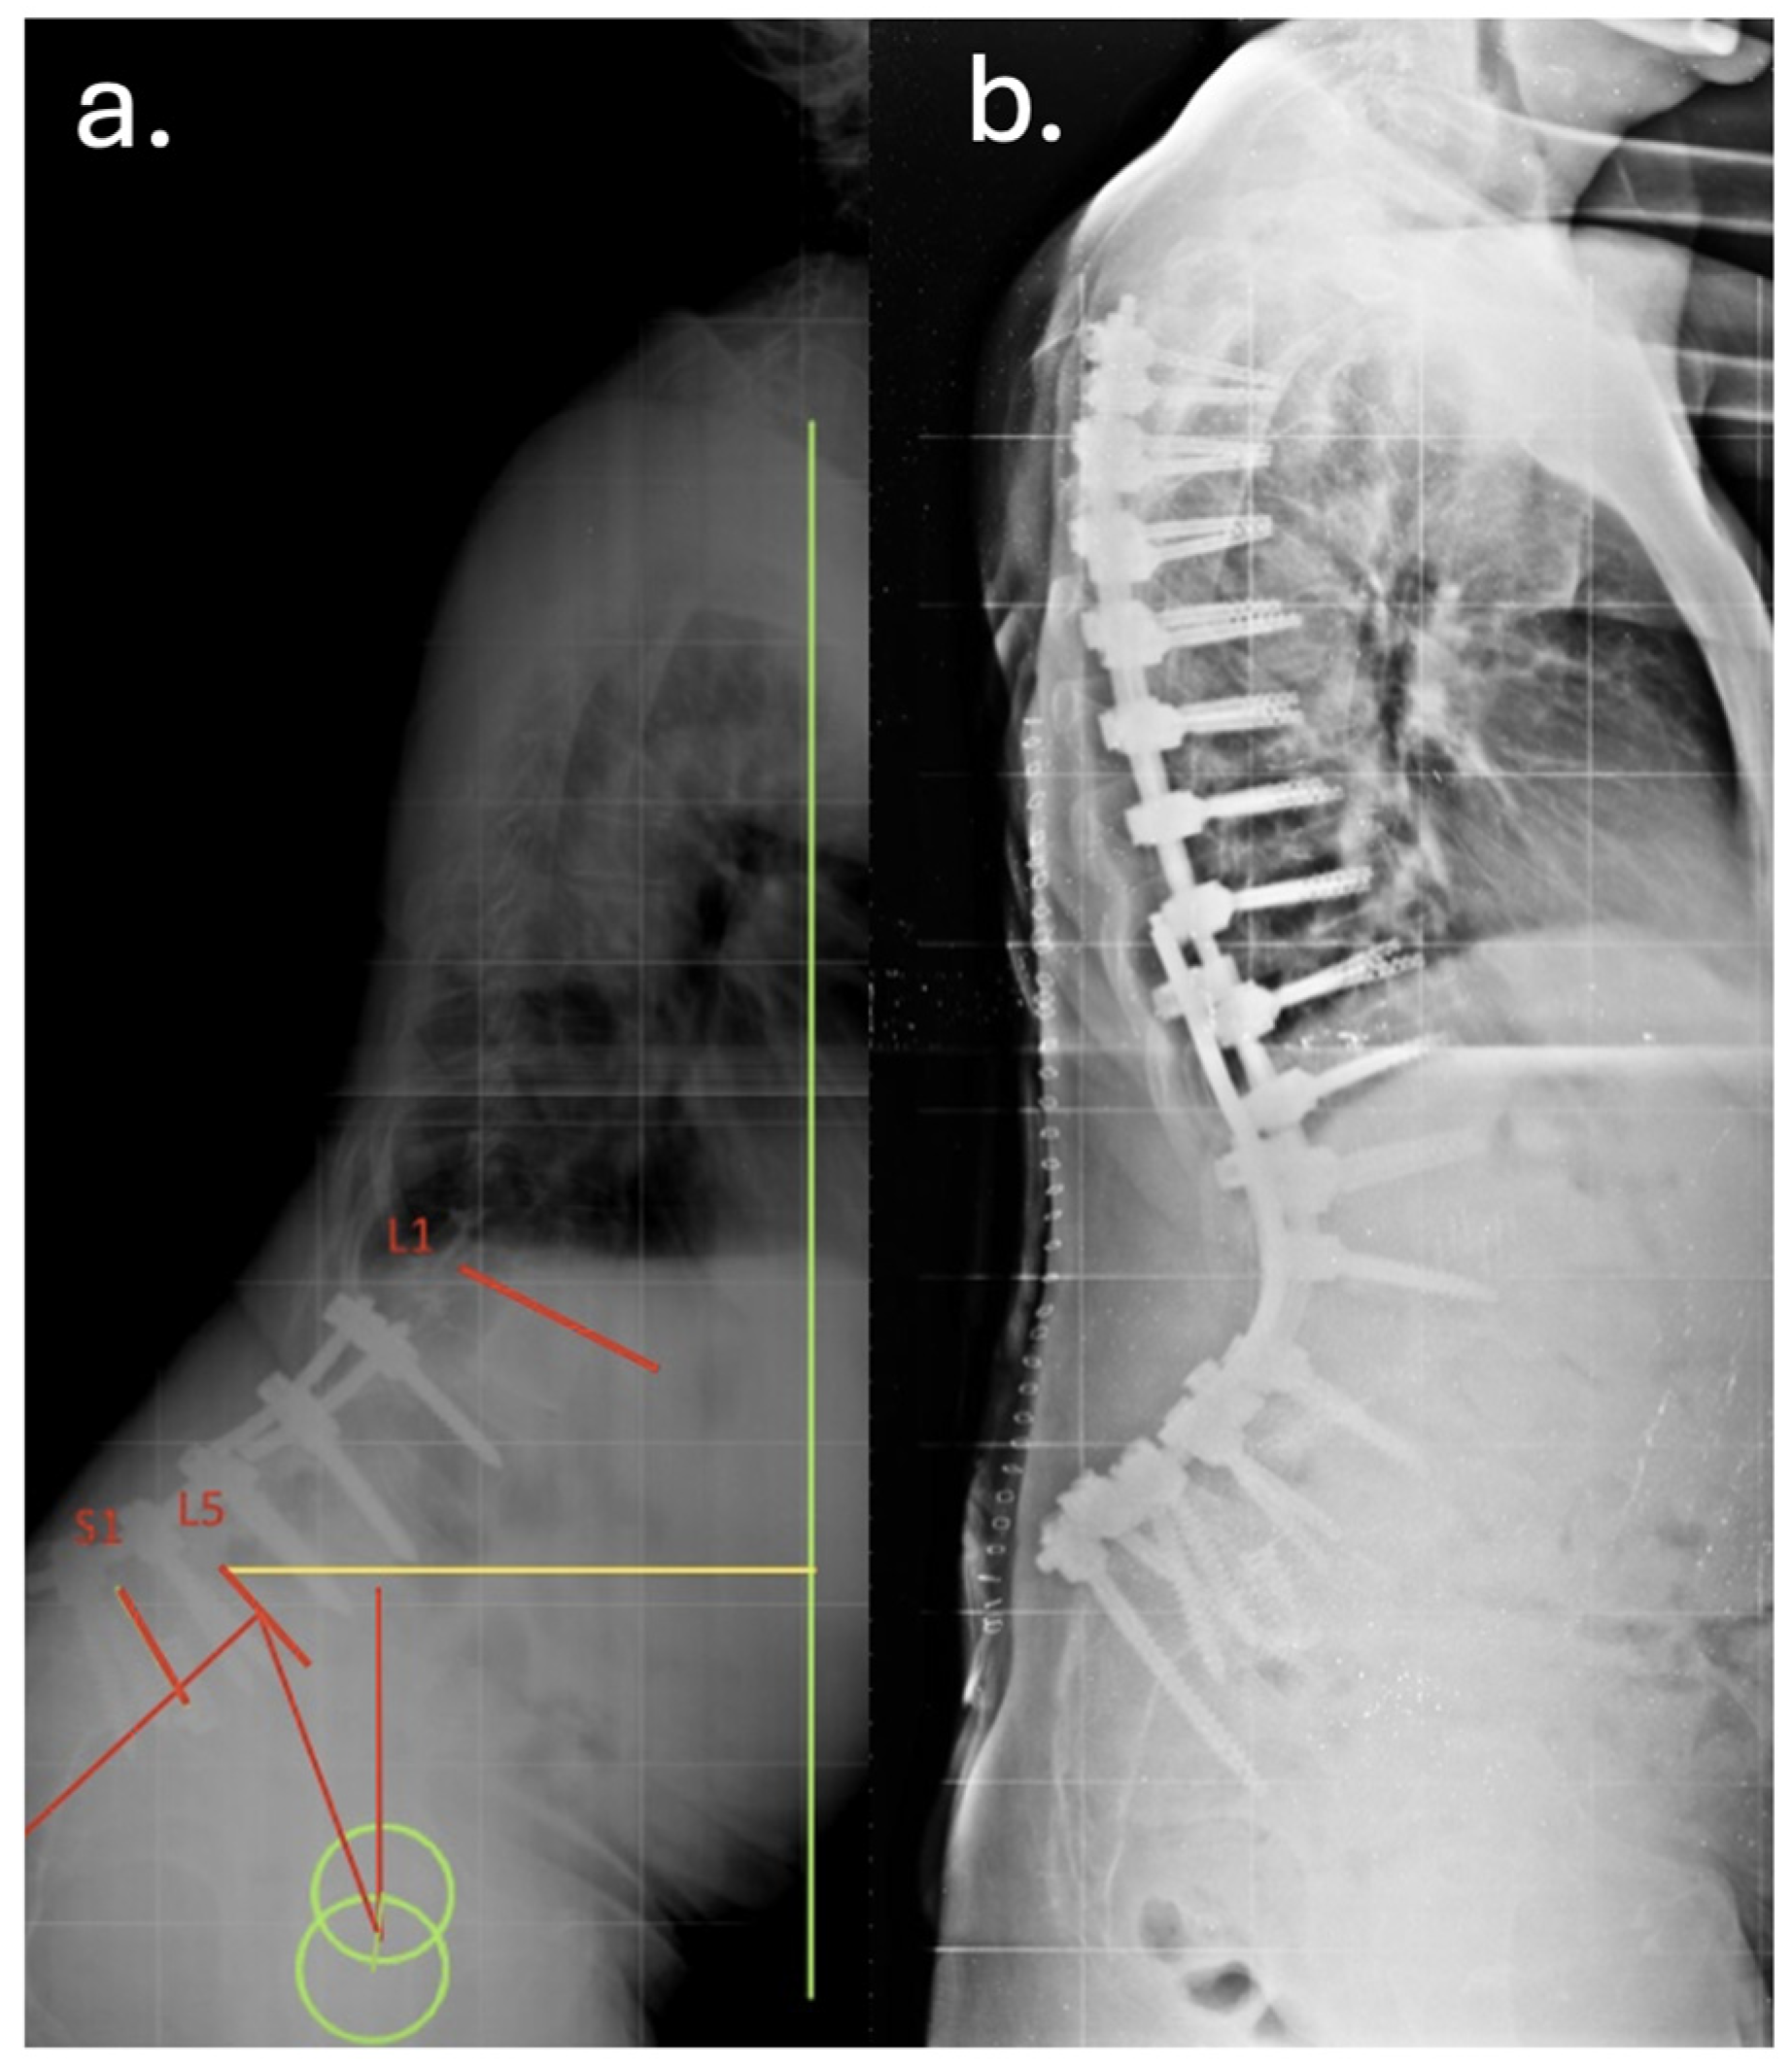

| Dec 2010 | Posterior decompression and L5–S1 fusion |

| Apr 2012 | Posterior extension of fusion to L3 for junctional failure |

| Nov 2014 | Extreme lateral interbody fusion (XLIF) at L3–L4 and L4–L5 |

| Jun 2016 | Major revision from T7 to pelvis with bilateral iliac fixation |

| Aug 2016 | Postoperative infection (Acinetobacter baumannii XDR), multiple antibiotic courses |

| Dec 2019 | Removal of left iliac and T4–T5 screws, new fixation at T2–T3 with 4-rod construct |

| Jan 2020 | Rotational musculocutaneous flap for soft tissue coverage |

| Feb 2022 | Diagnosis of sacral insufficiency fracture (CT: left sacral ala right ilio-pubic branch fracture, with loosening of iliac screws) |

| Sep 2022 | Surgical debridement, rod shortening, V-Y fasciocutaneous flap |

| Mar 2025 | Removal of fractured proximal thoracic screws; cultures positive for Staphylococcus epidermidis and Ralstonia pickettii |

| May 2025 | Stable condition on suppressive antibiotics; no further revision indicated |